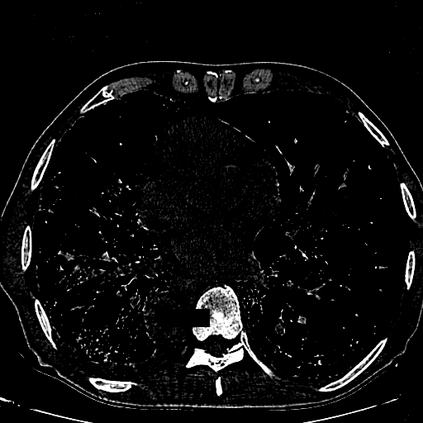

The novel coronavirus disease 2019 (COVID-19) has been spreading rapidly around the world and caused significant impact on the public health and economy. However, there is still lack of studies on effectively quantifying the lung infection caused by COVID-19. As a basic but challenging task of the diagnostic framework, segmentation plays a crucial role in accurate quantification of COVID-19 infection measured by computed tomography (CT) images. To this end, we proposed a novel deep learning algorithm for automated segmentation of multiple COVID-19 infection regions. Specifically, we use the Aggregated Residual Transformations to learn a robust and expressive feature representation and apply the soft attention mechanism to improve the capability of the model to distinguish a variety of symptoms of the COVID-19. With a public CT image dataset, we validate the efficacy of the proposed algorithm in comparison with other competing methods. Experimental results demonstrate the outstanding performance of our algorithm for automated segmentation of COVID-19 Chest CT images. Our study provides a promising deep leaning-based segmentation tool to lay a foundation to quantitative diagnosis of COVID-19 lung infection in CT images.

翻译:2019年新的冠状病毒疾病(COVID-19)在全世界迅速蔓延,对公共卫生和经济产生了重大影响;然而,对于有效量化COVID-19造成的肺感染,仍然缺乏研究;作为诊断框架的一项基本但具有挑战性的任务,分解在通过计算断层摄影(CT)图像测量的COVID-19感染的准确量化方面发挥着关键作用;为此,我们提出了对多个COVID-19感染区域进行自动分解的新型深层次学习算法。具体地说,我们利用综合残余变异学来学习一种稳健和直观的特征表征,并运用软关注机制来提高模型的能力,以区分COVID-19的症状。用公共CT图像数据集,我们验证了拟议的算法与其他相竞方法的功效。实验结果表明,我们自动分解COVID-19 Chest CT 图像的算法表现出色。我们的研究提供了一个充满希望的深度精细分解工具,为CT 图像中COVID-19肺感染的定量诊断奠定了基础。